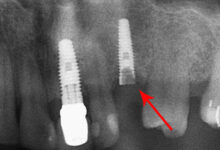

گزینههای جایگزین ایمپلنت دندان: راهحلهای اقتصادیتر

بریج (پل ثابت): جایگزین مؤثر دندان از دست رفته

بریج دندان بهترین جایگزین برای ایمپلنت دندان است، به خصوص اگر یک یا حتی دو دندان در کنار یکدیگر را از دست دادهاید. این روش شامل ساخت یک دندان مصنوعی (پونتیک) است که توسط روکشهایی که روی دندانهای طبیعی مجاور (پایه) قرار میگیرند، حمایت میشود. دندانپزشک ابتدا دندانهای مجاور را برای قرار گرفتن روکشها آماده میکند و سپس بریج ساخته شده در لابراتوار را روی آنها چسبانده و ثابت میکند. این روش کمهزینهتر از ایمپلنت دندان است و فرآیند درمان آن نیز سریعتر است، زیرا نیازی به جراحی و زمان طولانی برای بهبود استخوان ندارد.

- نیاز به تراشیدن دندانهای سالم: دندانهای طبیعی مجاور باید تراشیده شوند تا بتوانند روکشها را نگه دارند، که این موضوع میتواند به ساختار سالم دندان آسیب برساند.

- عدم تحریک استخوان فک: برخلاف ایمپلنت، بریج ریشه دندان را جایگزین نمیکند، بنابراین نمیتواند از تحلیل استخوان فک در ناحیه دندان از دست رفته جلوگیری کند.

- دوام محدود: بریجها معمولاً ۱۰ تا ۱۵ سال دوام میآورند و پس از آن نیاز به تعویض دارند.